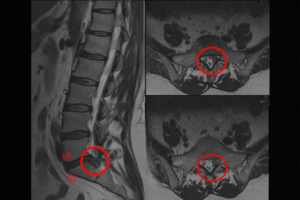

Kapalı bel fıtığı ameliyatı, mikroskop destekli, milimetrik kesiyle yapılan modern bir yöntemdir. Fıtık dokusu hassas şekilde çıkarılır, hasta aynı gün ayağa kalkar ve kısa sürede günlük hayatına dönebilir.

Bel fıtığı ameliyatı sonrası hızlı iyileşme için hastaların doğru pozisyonda dinlenmesi, ağır yüklerden kaçınması ve doktor tavsiyelerine eksiksiz uyması gerekir.

Dar kanal ameliyatı, omurga içerisindeki sinir veya omurilik üzerinde basıya neden olan darlıkları cerrahi müdahaleyle rahatlatmayı hedefleyen bir tedavi yöntemidir. Bu operasyon, hastalarda görülen yürüme zorluğu, uyuşma ve bel ağrısı gibi belirtilerin giderilmesinde yüksek başarı oranına sahiptir.

Bel kayması ameliyatı, omurlar arasındaki dengesizliği düzeltmek ve sinir üzerindeki baskıyı ortadan kaldırmak için yapılan bir cerrahi girişimdir. Amaç, omurgayı sabitleyerek hastanın ağrı ve hareket kısıtlılığı gibi şikayetlerini kalıcı olarak azaltmaktır.

Bel fıtığı, omurlar arasındaki diskin taşarak sinirlere baskı yapması sonucu bel ve bacaklarda ağrı, uyuşma ve hareket kısıtlılığına yol açan yaygın bir omurga hastalığıdır.

Omurga kırığı, omur kemiklerinde travma veya zayıflığa bağlı oluşan kırık sonucu sinir basısına yol açarak şiddetli ağrı, uyuşma ve felç riskine neden olabilen ciddi bir durumdur.

Omurga kırığı ameliyatı, kırık omurun stabilitesini sağlamak ve sinir basısını gidermek amacıyla yapılırken; vertebroplasti, çökme kırığı olan omura kemik çimentosu enjekte edilerek ağrıyı azaltan ve omurgayı güçlendiren minimal invaziv bir yöntemdir.

Dar kanal ameliyatı, omurga kanalındaki sinir sıkışıklığını gidererek hastanın yürüme ve yaşam kalitesini artırmayı amaçkar; vidasız dar kanal cerrahisi omurgaya vida yerleştirilmeden, doğal yapıyı koruyarak yapılan modern bir tedavidir

Boyun fıtığı, boyun omurları arasındaki diskin kayarak sinirlere baskı yapması sonucu ağrı, uyuşma ve güçsüzlüğe neden olur; ilaç ve fizik tedaviye rağmen şikâyetlerin düzelmediği veya ilerleyici sinir basısının görüldüğü durumlarda cerrahi uygulanır.

L5-S1 bel fıtığı, bel omurgasının en alt seviyesinde diskin dışarı taşarak siyatik sinire baskı yapması sonucu bel ağrısı, bacak ağrısı, uyuşma ve hareket kısıtlılığına yol açan yaygın bir durumdur.